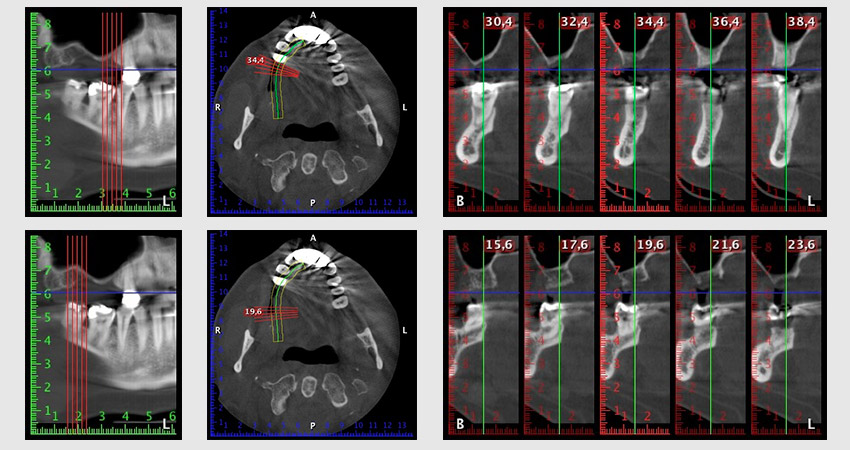

Al fine di pianificare e minimizzare i rischi, circa sei mesi dopo l'estrazione dei denti 16 e 14 viene effettuata una tomografia digitale volumetrica (DVT, Planmeca), la quale conferma chiaramente la mancata rigenerazione ossea nel volume desiderato (da fig. 2 a 7).

Per ridurre l'accrescimento nella regione 14, con il consenso della paziente si opta per il posizionamento e l'inclinazione dell'impianto 16 in direzione dorso-craniale (fig. 8).